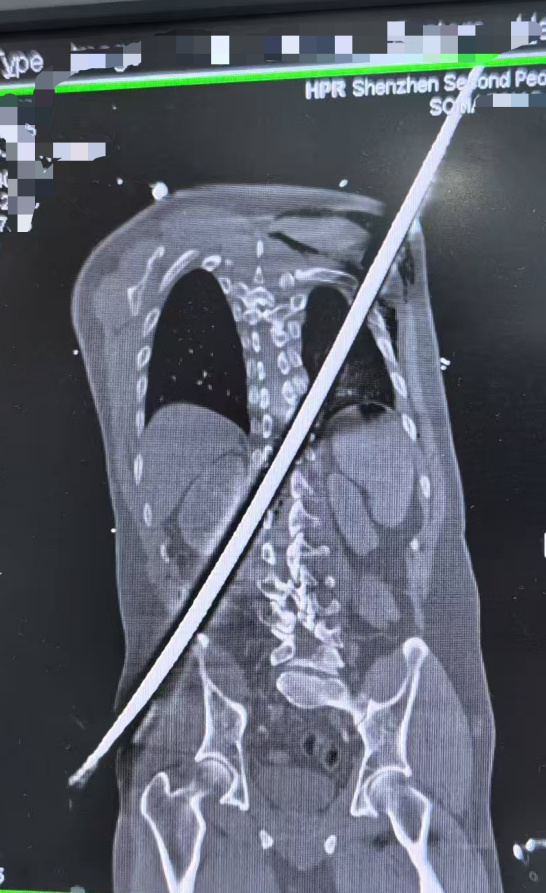

一场工地意外,让男子遭遇了致命重创。一根粗壮的钢筋,以67厘米的长度,从他右侧臀部刺入,斜穿躯干,最终从左后侧肩背穿出。

被紧急送到深圳二院时,患者已经陷入休克,生命体征微弱,随时可能离世。CT检查更让医护人员倒吸一口凉气:钢筋紧贴大血管、肾脏,击穿脊柱椎管,患者双下肢无法活动,稍有晃动就可能引发瞬间大出血。

专家团队根据CT影像精准判断:钢筋穿行路径极度凶险,如同在体内“走钢丝”,手术必须快、准、稳,一旦失误就是致命风险。医院当即决定:立即手术,全力一搏。